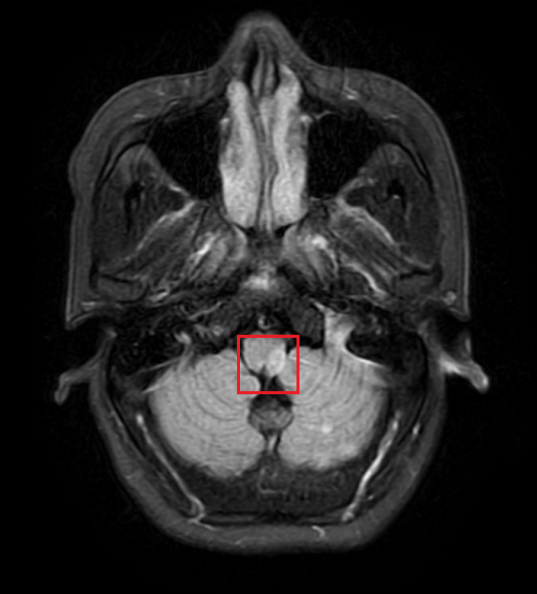

(张大伯脑梗影像图)